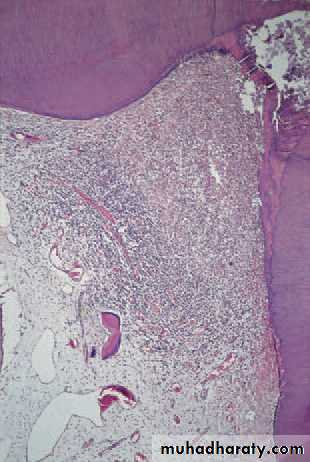

Acute pulpitis. Low-power view showing occlusal caries penetratingto the pulp through a layer of reactionary dentine. There is acuteinfl ammation localised to the pulp horn.

Acute pulpitis. Beneath the carious exposure (top right) a denseinfl ammatory infi ltrate is accumulating. More deeply, the pulp is intenselyhyperaemic.